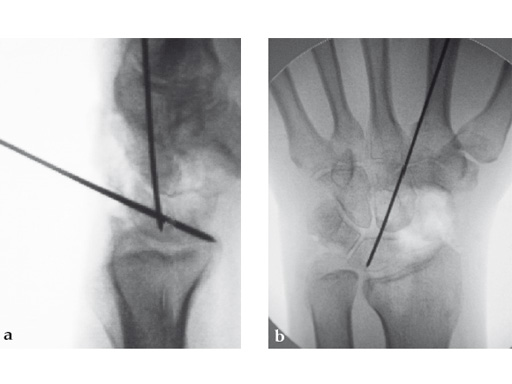

Fig 2ab Dorsal intercalated segment instability correction and K-wire fixation.

Fig 3ab Bone debridement. Guide positioning and fixation.